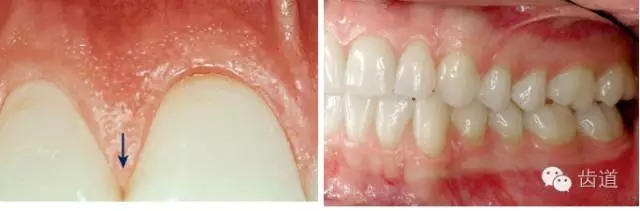

2、牙齦

5.webp.jpg

(顏色、形狀、質(zhì)地、退縮、BOP、PD、附著齦)

6.webp.jpg

7.webp.jpg

8.webp.jpg

9.webp.jpg